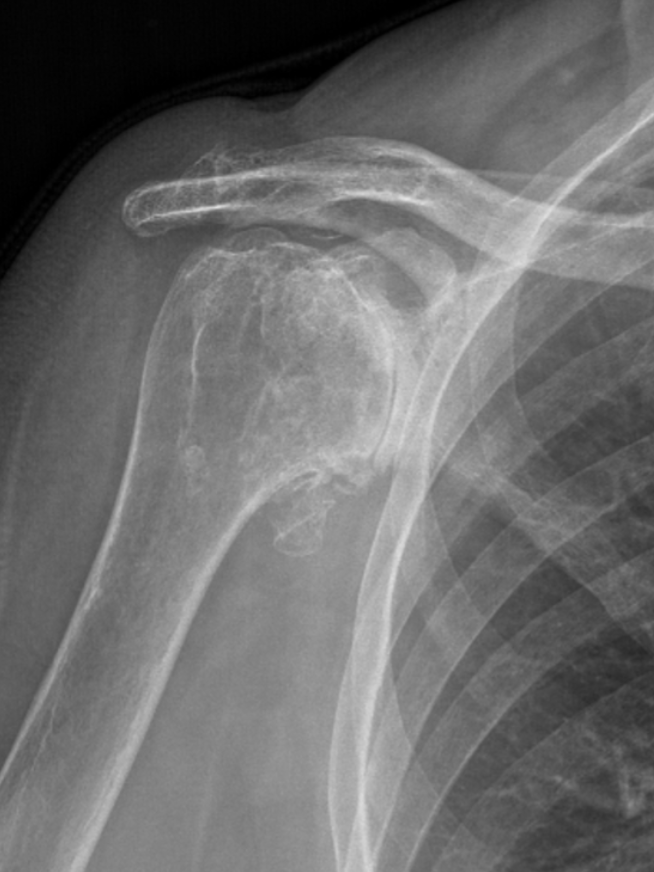

Concentric Arthritis

Eccentric Arthritis